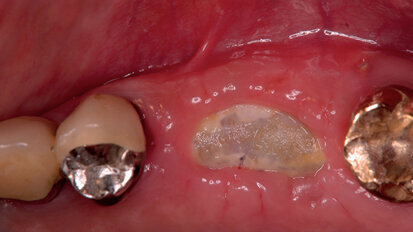

Procedure mininvasive d’aumento e preservazione alveolare (open barrier membrane technique)

Le membrane convenzionali in PTFE espanso (ePTFE) sono state ampiamente usate per la rigenerazione guidata (GBR) e sono divenute uno standard negli anni ...